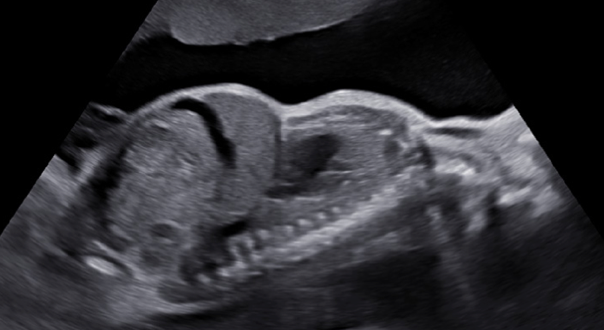

Fig 1. Torace îngustat